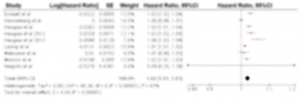

心室不整脈(VA)予測のゴールドスタンダードと言えば左室駆出率(LVEF)ですが、致死性VAを発症した患者の約4割はLVEFが保たれていたという報告もあり(J Am Coll Cardiol 2017; 68: 556-569)、LVEFに替わる予測マーカーが議論されてきました。そこで近年注目されているのがストレインエコーです。より正確に、そして優れた再現性をもって局所心筋の評価が可能であり、そのイベント予測精度はLVEFを上回ることが報告されています(Heart 2014; 100: 1673-1680)。最近、このストレインエコーを用いて測定した左室ストレインのばらつき(LV mechanical dispersion)とVAの関連性が注目されています。しかしながら、LV mechanical dispersionとVAの関連を調べた研究の多くは単施設かつ少数例での検討であり、また、その患者背景は様々です。そこでエビデンスを強化すべくメタ解析に挑戦しました。結果はLV mechanical dispersionはVAの独立した予測因子であり、その予測能は従来の指標を上回るというものでした。現在論文を投稿中です。

図1. (J Am Soc Echocardiogr 2012; 25: 667-73より引用): VTを発症したDCM患者(左)の方がストレインのばらつき(Dispersion)が大きい。

図2. メタアナリシスの結果(まだ詳細は提示できません)。早く日の目を見ますように。